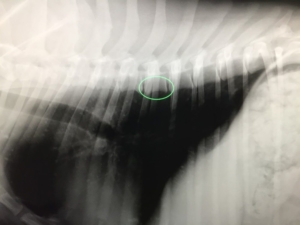

レントゲンなどを撮って確定診断できることはあまりありません。

背中を押すと嫌がるような症状があり、血液検査などで炎症反応が強まっていれば椎体炎を疑うっていきます。

詳しく調べるのであれば、MRIを撮ることによって椎体の炎症を確かめることになりますが、感染を起こしているのがあくまでも体の深部なので、そこから細菌を分離することは非常に難しいと思います。